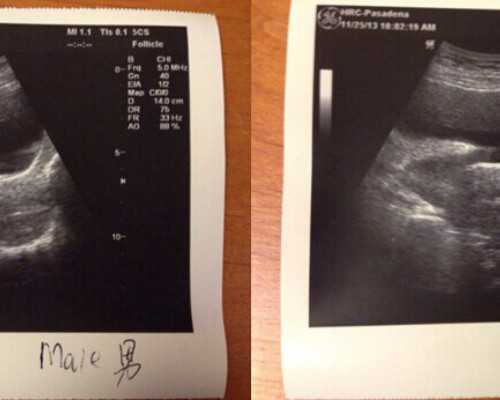

5、胚胎培育第一天,可以了解到受精的胚胎有多少,第3~5天可以知道胚胎的质量、等级、性别。